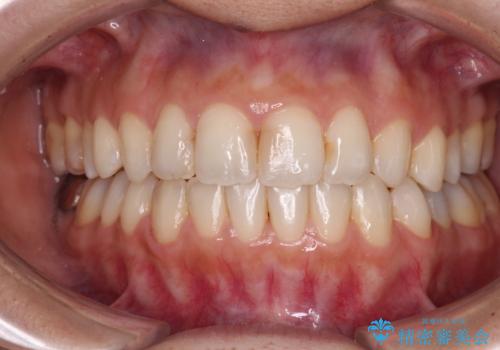

気になる出っ歯をインビザラインで改善

治療期間は長くなりましたが、出っ歯が改善することができました。

治療を行いながら、果たして奥歯の咬み合わせを改善することができるのかという不安はありましたが、結果としては理想的な咬合を獲得することができました。

口が閉じやすくなり、患者様には大変満足していただきました。